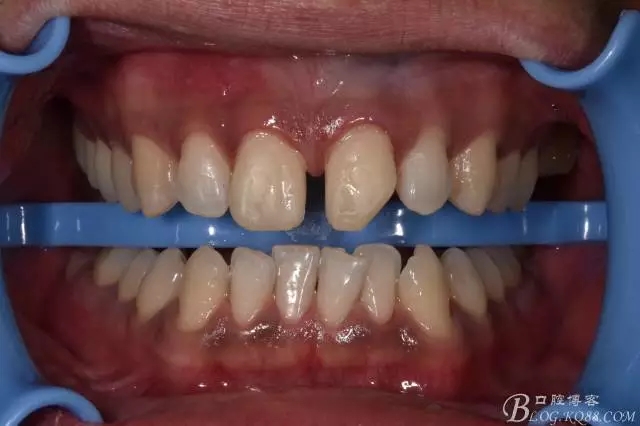

主訴:要求修復門牙缺損并關閉縫隙

現(xiàn)病史:患者自述三年前外傷致左上門牙缺損,并自覺門牙有縫影響美觀,要求治療。

檢查:左上一遠中切角缺損,少量牙本質暴露,冷熱刺激稍敏感,叩(-),不松動,牙齦無明顯異常。右上一正常。門牙間隙約3MM左右。

1比色 個人傾向于2L1.5色,但小伙子堅持2M1色,因為要白一點。

640.webp.jpg